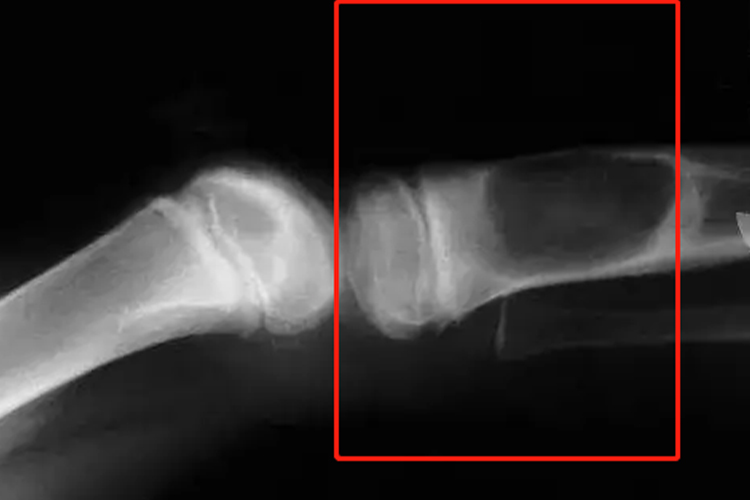

好发于股骨下端、胫骨上端、肱骨近端干骺端内。临床表现为疼痛、局部肿胀,如肿瘤累及邻近的关节,使关节出现不同程度的功能受累,表现为屈伸疼痛和受限,以及跛行等。影像学检查可见骨质破坏。